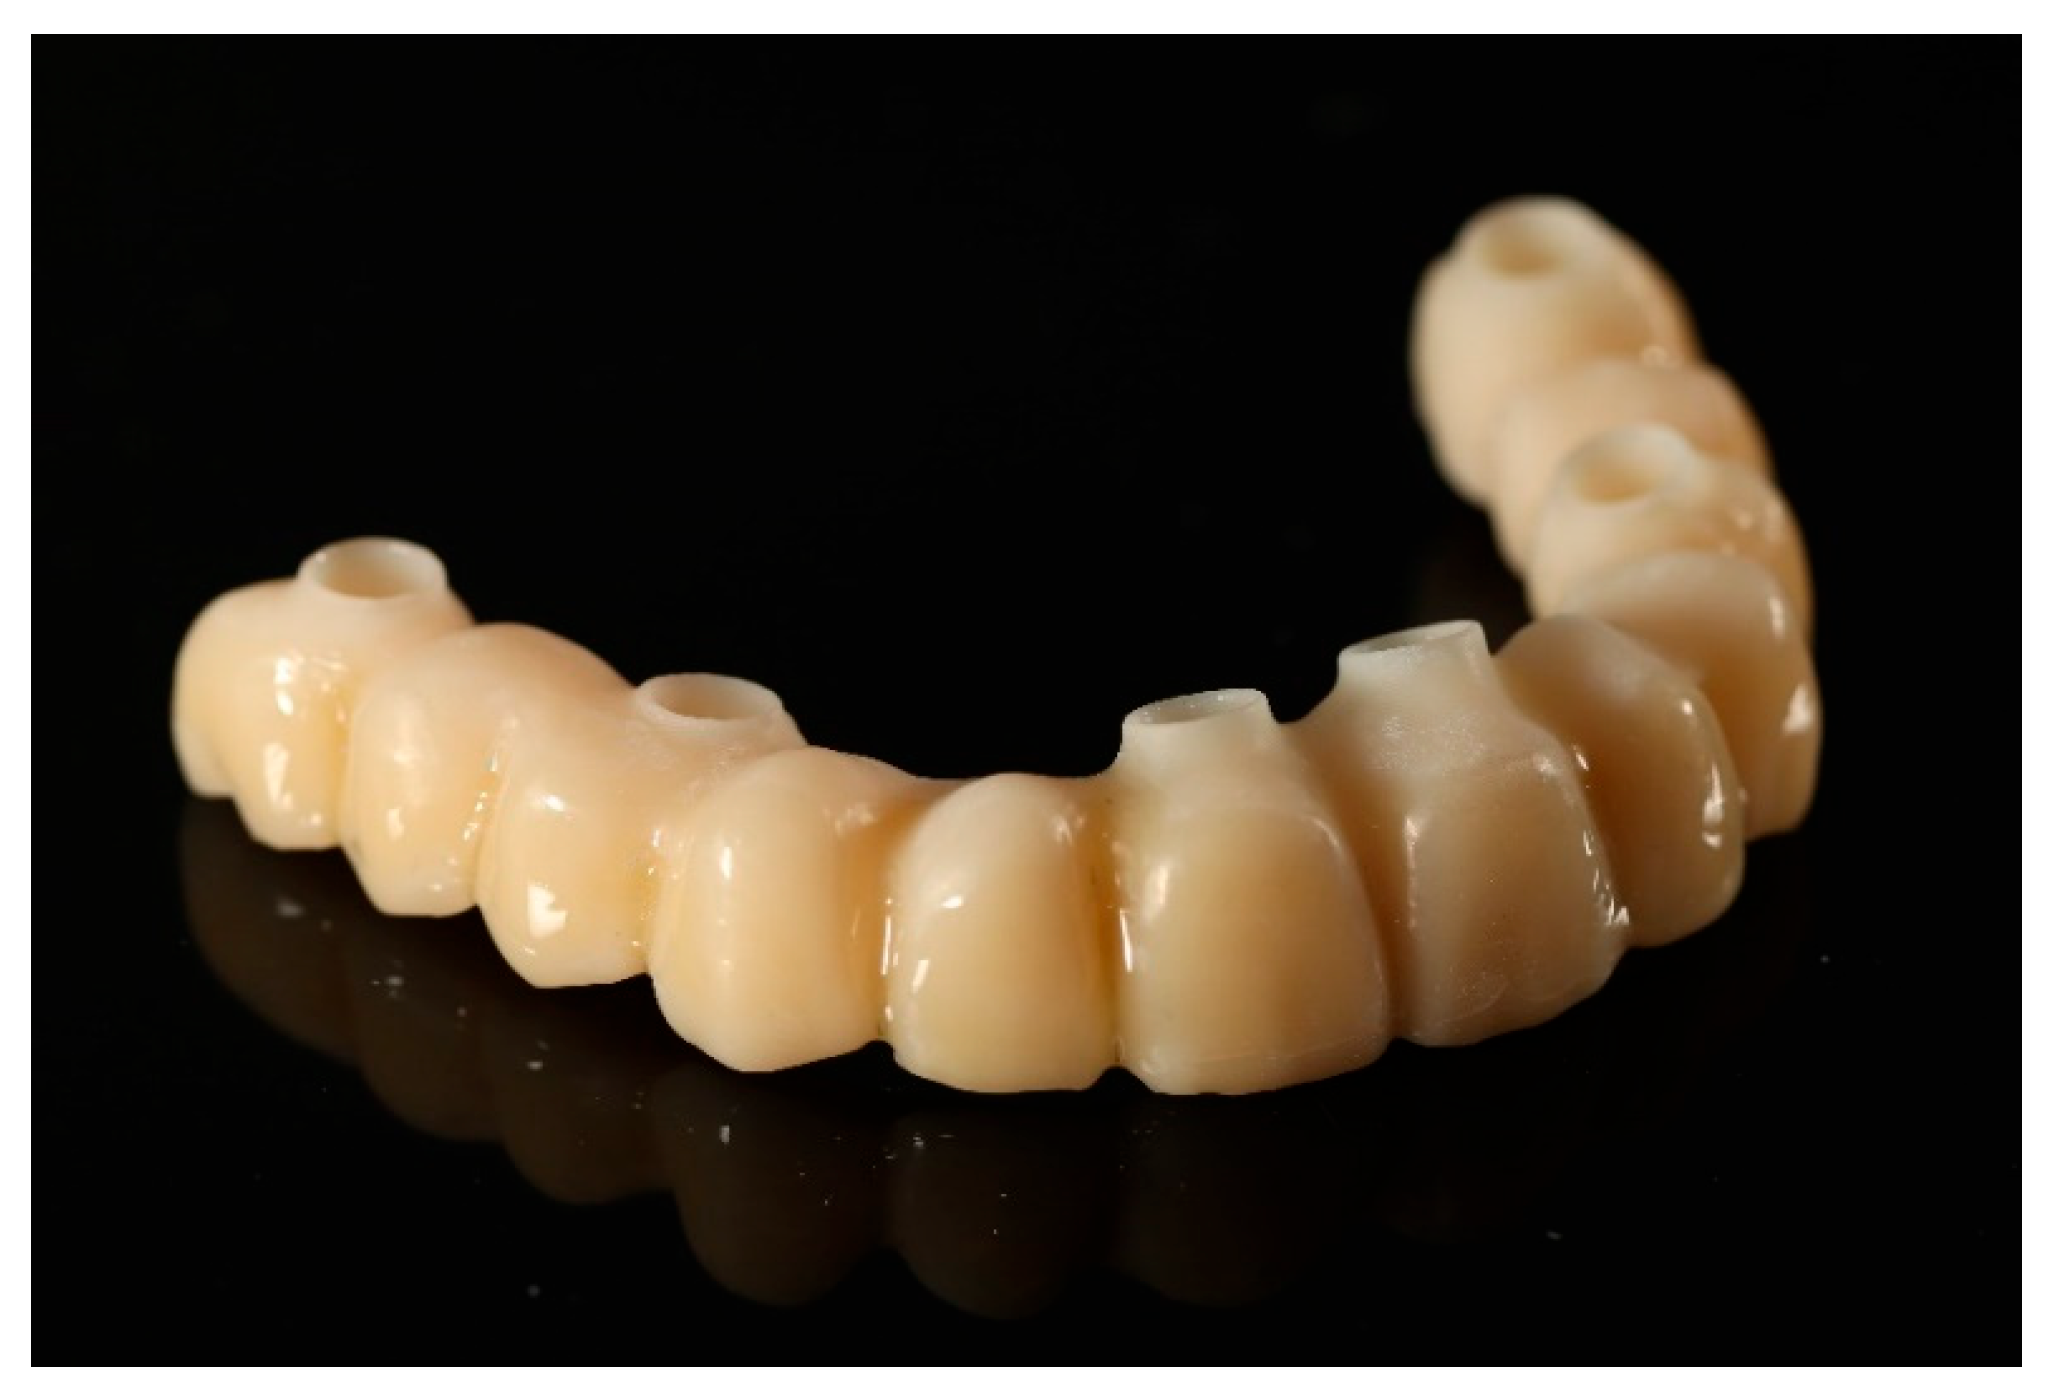

Following the confirmation of the passive fit, and a successful clinical try-in, the definitive full-arch prosthesis was fabricated as a monolithic zirconia superstructure on the same titanium framework (Figure 17) and delivered to the patient.

A custom-milled titanium framework provided rigidity and long-term stability. A monolithic full-contour zirconia superstructure was manufactured and bonded onto this framework, ensuring both mechanical strength and enhanced aesthetics. Recent reports confirm that zirconia-on-titanium combinations offer predictable outcomes in terms of aesthetics, function, and biological response [27].

Figure 17. Definitive full-arch prosthesis fabricated on the titanium framework (material: monolithic zirconia).